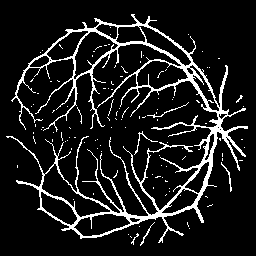

Vessel Extraction

Experiments are implemented on the Digital Retinal Images for Vessel Extraction database (DRIVE) proposed for studies on the extraction of blood vessels (Staal et al. 2004). Models are trained after reshaping all data at 256256 size. Rand score and information theoretic score is also used as evaluation metrics.

The following provides quantitative comparisons of three FCNs respectively. Example results on various image-to-image mapping tasks are shown in Figure 2.

Table 2 lists the best evaluation results. It shows that our model performs on par with U-Net and better than FCN-16s.